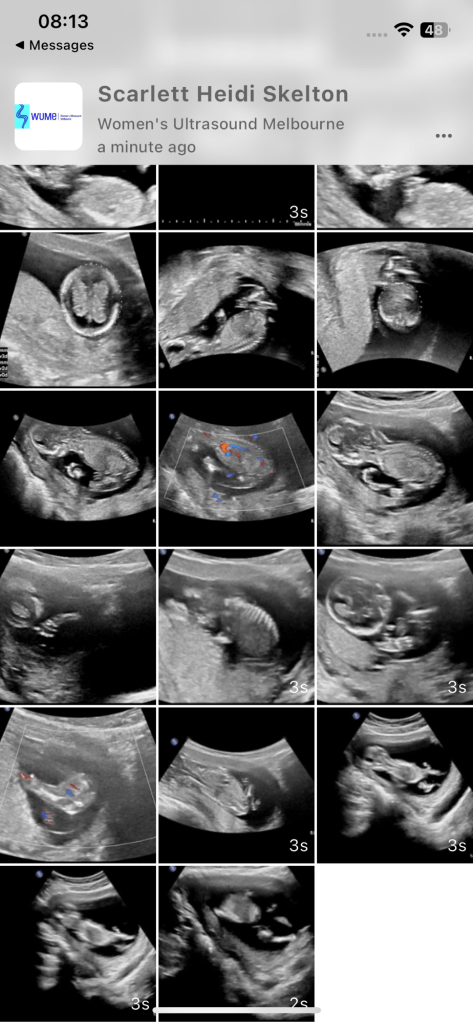

Die erste Woche war ich im Schock. So viele Pläne mussten umgedacht werden, von null auf 100 veränderte sich gefühlt alles. Was sehr fest half, war, dass Harry sich soooooooooo fest freute. Ab der Sekunde 1, in der er erfuhr, dass ich schwanger bin, transformierte Harry zu einem Superhero. Er kocht mir ein bis drei Menus pro Tag, weil ich immer hungrig bin, und organisiert ganz fleissig Babykleider, Schwangerschaftskleider, Möbel fürs Babygirl-Zimmer und alles sonst, was es braucht. Währenddessen vegetiere ich, wann immer möglich, auf dem Sofa, idealerweise mit eiskaltem Wasser und Crackers. Die Hitze ist nicht mein Freund in diesem Jahr. Am liebsten bin ich im kalten Wasser oder im heruntergekühlten Schlafzimmer. Ich fand in der 4. Woche heraus, dass ich schwanger bin. Bereits 4 Wochen? Fragte ich mich. Heute bin ich in der Woche 18 Tag 1 angekommen. Noch 22 Wochen. Bald Halbzeit. Das erste Trimester (Woche 0-13, aber besonders so Woche 10-13) (so viele neue Wörter) war so mittel cool. Es war mir eigentlich immer schlecht, ich habe am liebsten nur Brot und Crackers gegessen, ich war müde und unternommen habe ich nur so viel wie notwendig. Besonders streng waren die Wochen 10-13, als die Ferien vorbei waren und ich wieder arbeiten musste. Das war so streng. Am Ende der ersten Arbeitswoche hatte ich eine Mini-Krise, wie dies zu schaffen ist. Doch mit jeder Woche sind die Schwangerschaftssymptome ein wenig weniger geworden und ich habe mich wieder an den Schulalltag gewohnt. Aller Anfang ist schwer. Ich finde es noch immer eine unglaubliche Leistung, als Frau 100 % zu arbeiten und gleichzeitig schwanger zu sein. Nach der Arbeit gibt es nicht mehr viel ausser essen und schlafen, wenn ich ehrlich mit mir selbst bin. Nun. In Zeiten, in denen mich das frustriert, denke ich daran, dass ich ganz bestimmt nur zweimal im Leben schwanger sein werde und es eine Phase ist, die auch wieder vorübergeht. Zudem ist es auch magisch. Ein kleines Mädchen wächst in mir heran. Ich freue mich bereits jetzt auf all das Chaos, das sie anrichten wird, dass wir eine kleine Mini Version von Harry und mir in unserem kleinen glücklichen Leben willkommen heissen zu dürfen und das Leben mit ihr zu teilen. Was auch grossartig ist, dass sie gesund ist. Bei jedem Ultraschall (bis jetzt 2) und Bluttest (einmal) bekommen wir immer super Werte, das macht die Schwangerschaft sehr positiv. Ich bin zudem sehr froh, ist nun das Risiko einer Fehlgeburt, mit dem Ende der 13. Woche, sehr, gering. Bis zur 13. Woche ist es irgendwie komisch. Ich freute mich so sehr, doch traute mich auch nicht, mich zu fest zu freuen, weil was, wenn… Nun, das ist nun hinter mir und wir schreiten Vollgas in dieses neue Kapitel voller Babypoo und Kindergeschrei. Ich freue mich sehr, wirklich sehr. Auch darauf, Harry als Papa zu erleben. Harry wird der beste Papa überhaupt.

Nach Tasmanien fand der erste Ultraschall statt, wir dachten, dass wir in der 8. Woche waren. Doch die Frauenärztin bemerkte, dass dieses Baby bereits 10 Wochen alt sein musste. Hervorragend – 2 Wochen weniger Schwangerschaft.